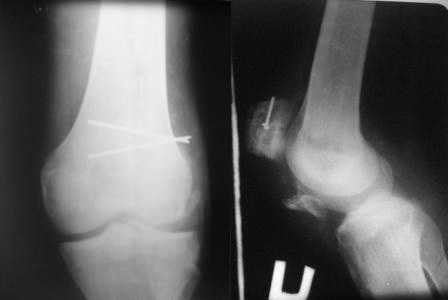

Обратился б-ной С. 1986г.р с застарелыми переломами надколенника и таранной кости, сросшийся переломом обеих локтевых отростков. 25.07.07.г. упал с 6-го этажа. Оперирован в г. Тюмени в гор. б-це 15.08.07.г.:Судя по рентген снимкам остеосинтез обеих локтевых отростков по Веберу, остеосинтез правого надколенника (каким способом не понял ), фиксация гипсовой повязкой правой н/к, гипс снят через 40 дней (со слов б-го.) Обратился в начале декабря, с жалобами на отсутствия активного разгибания в пр. коленном суставе, боли и отечность в обл. пр. г/стоп. сустава и стопы. Больной ходит самостоятельно с палочкой, сильно хромает на правую ногу, гипотрофия квадрицепса, активное разгибание abs, в обл. г/стопного сустава умеренная отечность, актив. и пассив. движения почти в полном объеме, слегка болезненная, при осевой нагрузке боль усиливается, Сделана Р-графия локтевых суставов, пр. коленного и г/стопного суставов. Спицы и проволоки из локтевых отростков удалены. Я больному обещал, что выйду на форум, посоветуемся и вместе решим, что делать. 1. Из -за ретракции м/тканей репозиция отломков надколенника не удается, что делать? 2. Перелом таранной кости- вроде схватка имеется но с кистозными изменениями, может не трогать? Заранее благодарю !!

прилагаю снимки надколенника.

В приложении фото пациента с переломом надколенника 3 месячной давности. После мобилизации отломков, 4 главой мышцы бедра и полного разгибания голени оставался диастаз между костными фрагментами в 2 см. В связи с этим наложили модуль из аппарата Илизарова - 2 опоры и 2 спицы (в верхнем полюсе надколенника и верхней трети большеберцовой кости). Очень медленно (в течение 15 минут) путем накручивания гаек на стержнях растянули 4 главую мышцу бедра и устранили диастаз. Аппарат демонтировали и выполнили остеосинтез <стягивающей петлей>. Через 6 месяцев фиксаторы удалены. Автор данного <хирургического трюка> профессор из Австрии Vilmos Vecsei (<Гений ортопедии>, 2004, № 4, С. 94-95). Ваш случай не совсем идентичный по давности травмы и малой величине дистального отломка, но описанный <трюк> может оказаться полезным и при выполнении операции, которую рекомендует Джолдас.